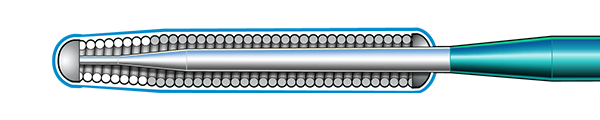

Inner Coil Technology

The advanced design of the stainless steel core and Inner Coil Technology provides a unique combination of exceptional torqueability, rail support, and shape retention.

- Stainless steel inner coil affixed directly to the distal end of the guidewire core

- Improved durability and ease of shaping

- Exceptional torqueability without whipping

Micro EMTTM Technology

MICRO EMT exactly matches the taper of the core and coil, allowing for a lower profile and a more flexible core, leaving almost no room for the core to move within the coil, resulting in 1:1 torque.

- Entry: The smallest tip on the market (0.008”) and the long taper (6 cm) facilitate easy lesion entry in even the most complex lesions.

- Maneuverability: A flexible distal shaft enables excellent intraluminal navigation in complex lesions, with minimal perforation risk.

- Torque: With exactly matched tapers, the core and coil move as one, eliminating whip and empowering precise steerability.